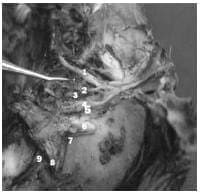

3. Contenido del Seno Cavernoso derecho con clinoidectomía anterior.

1-Apófisis Clinoide posterior.

2-II par.

3- Membranas anteriores

4-Adherencias venosas a la Carótida intra cavernosa.

5-A. Meníngea dorsal

6-VI par.

7-G. Gasser, III y IV par replegados.